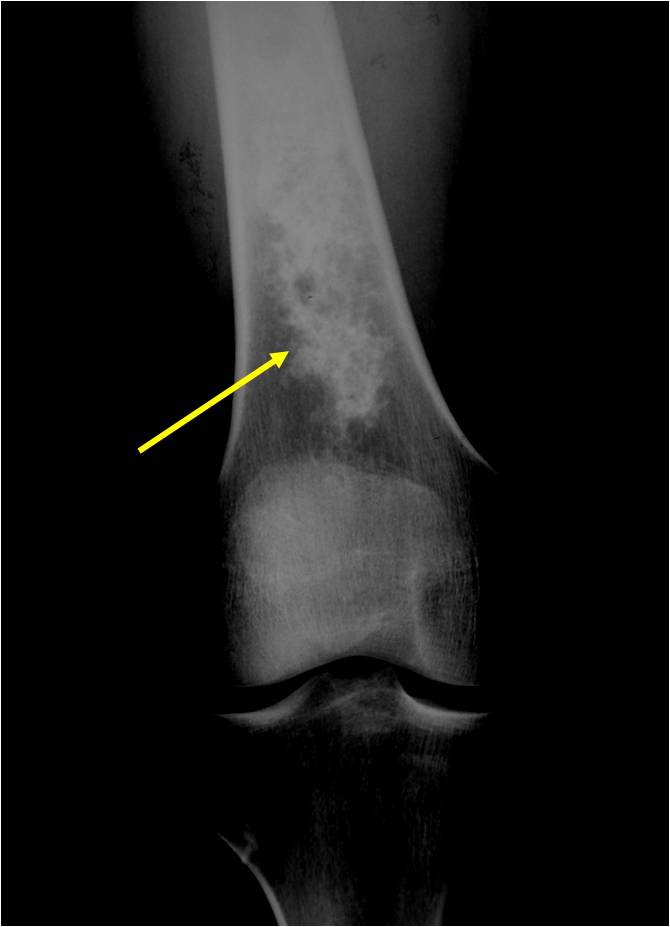

Radiographic Presentation

- Localized, radiolucent defect usually with punctate calcifications

- Calcifications are typical but not always present

- Matrix may demonstrate various degrees of calcification

- Calcifications are stippled, punctate, popcorn like calcifications and “Ring and Arc” calcifications

- Cartilage tumors grow in a lobular manner. The perimeters of the lobules undergo

- enchondral ossification that may calcify. If the entire perimeter of the lobule calcifies it appears

- radiographically as a “Ring”. If a portion of the perimeter of a lobule calcifies it forms an “Arc” on

- an X-ray.

Plain X-Ray:

- Geographic lytic lesion

- Central often metaphyseal in long bones

- Can be eccentric also

- Expansile remodeling with thinned cortex

- Chondroid matrix with calcifications in majority of tumors

- Approximately 20% have limited or no calcifications